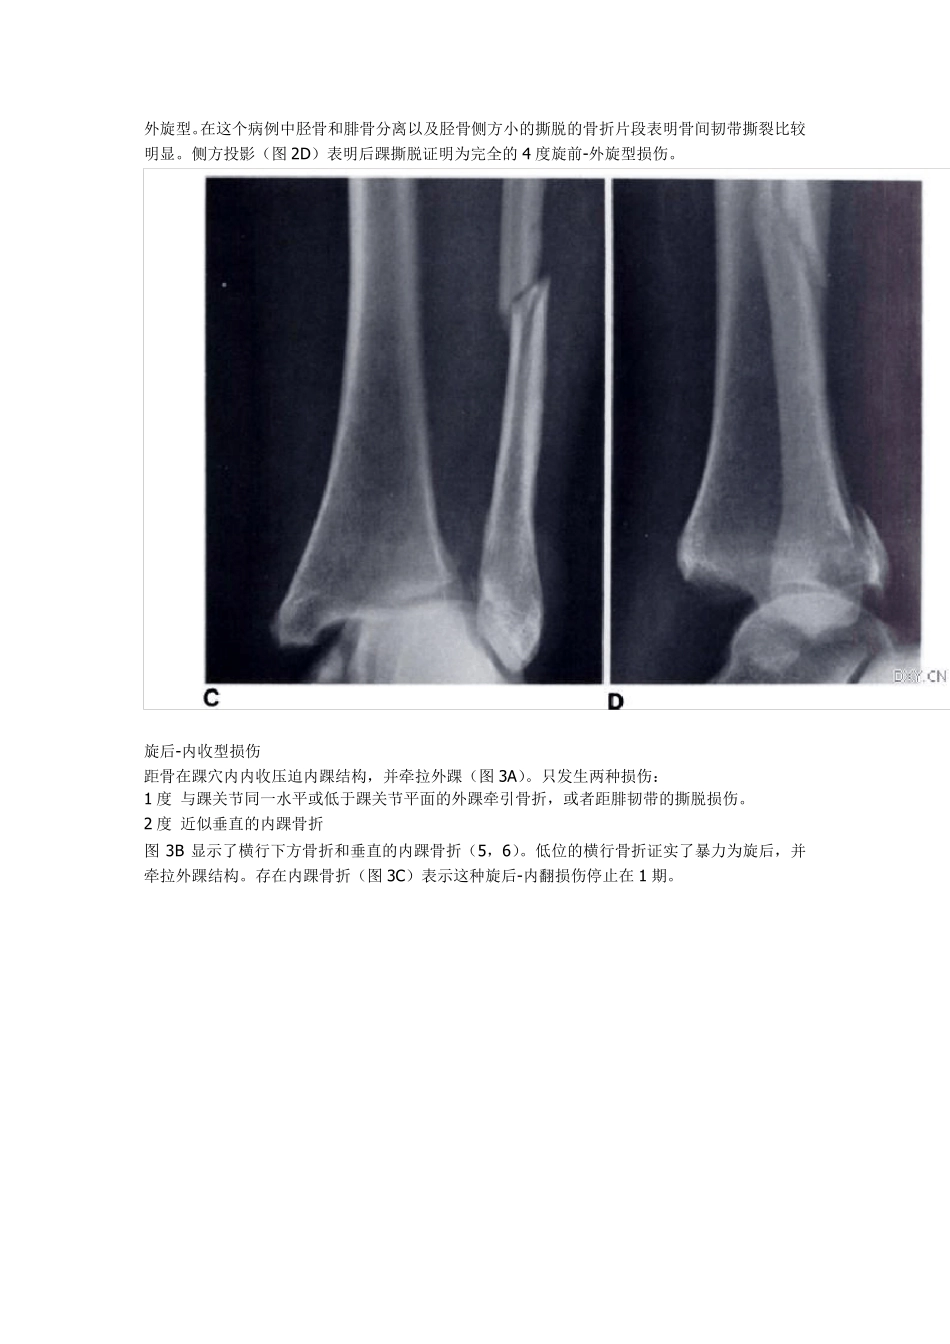

踝关节骨折分类系统(Lauge-Hansen 分型):一种评估系统 Department of Radiology, Los Angeles County-University of Southern California Medical Center, 1 200 N. State St., Los Angeles, CA 90033. Address reprint requests to D. M. Forrester 1950 年Lauge-Hansen 医生依据损伤时足的位置和导致畸形的暴力提出了踝关节骨折的分类系统。骨科医生广泛应用这个系统,但是放射学科医生通常不应用这个分类系统。作者提出一种系统能够快速评估90%-95%病例的损伤机制。发现骨折并对损伤进行分类并能够做出韧带损伤的诊断。以腓骨骨折为依据,可以立即发现四种类型的损伤:旋前-外展型,旋前-外旋型,旋后-内收型,旋后-外旋型。随后评估内踝骨折和后踝骨折,确定损伤的程度和韧带撕裂的部位。 1950 年Lauge-Hansen 依据损伤时足的体位和所受外力对踝关节损伤进行分类1,2。他的研究性工作已经被广泛应用,作为评估踝关节损伤的依据。 通过将尸体足固定在板上,给予不同的应力,Lauge-Hansen 建立了四种类型的踝关节损伤类型:旋前-外展型,旋前-侧旋型(外展),旋后-内收型,旋后-侧旋型(内翻)。双词语命名的第一个词指受伤时足处的位置;第二个词语是指发生变形的暴力。他发现对于踝关节的暴力造成的韧带和骨骼的损伤是按照可以预测的顺序发生的。如果暴力在发生顺序任何一点停止,导致不完全的系列损伤3,4。因此如果知道受伤时足所处位置和所受暴力的方向,可以在 X 线片上对不能显现的韧带损伤和明显的骨折作出评估。 尽管应用 Lauge-Hansen 分型可以作出精确的和复杂的放射学报告,但是为什么没有被广大放射学科医生普遍应用呢?为什么一直应用单纯描述性词语例如“内踝骨折”或“三踝骨折”作为诊断呢?单纯内踝骨折可能反映旋前或旋后损伤。与之相似,“三踝骨折”可能是旋前-侧方旋转或旋后-侧方旋转损伤的末期。如果骨折复位以发生损伤的暴力为反方向,判定损伤机制是重要的。 不幸的是,当病人发生踝部骨折时,通常不能表述事故发生时足所处的位置。与实验情况不同,放射医生必须从骨折特异性位置和形态重建信息。 应用 Lauge-Hansen 分型我们设计了一种规则系统可以快速评估损伤机制。识别踝部骨折块的数量能够证实损伤是否完全或在中间停止。从这方面信息,从骨折类型可以推断出韧带损伤情况。 四种损伤机制 内旋-外展 当足内旋时,距骨在踝穴内外展这导致牵引内侧结构并压迫外侧...